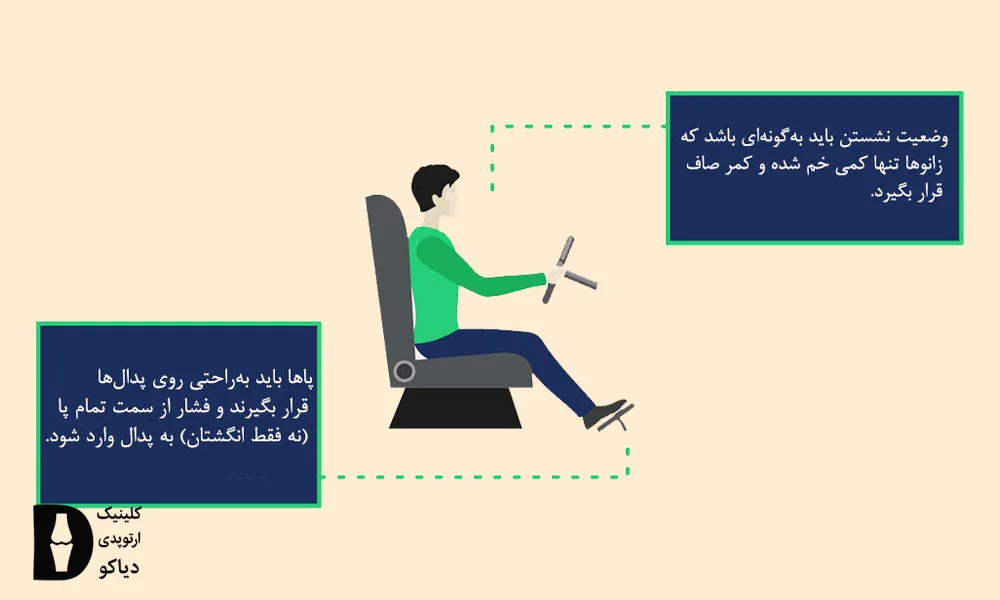

برای رانندگی طولانیمدت

بر اساس منابع بالینی فشار مداوم روی پا، علائم هالوکس والگوس را تشدید کند. یکی از مواردی که باعث فشار مداوم روی پا میشود، رانندگی است. این موضوع بهویژه هنگام مسافرت و برای افرادی که شغلشان رانندگی است، اهمیت دارد.

برای پیشگیری از بروز مجدد این عارضه لازم است حالت صحیح بدن و پا هنگام رانندگی رعایت شود. برای این کار صندلی خودرو باید جوری تنظیم شود که زانوها تنها کمی خمیده باشند و پا به طور کامل روی پدال قرار بگیرد. همچنین رعایت نکات زیر هنگام رانندگی تأثیر بسیاری در پیشگیری از عود مجدد انحراف انگشت شست دارد.

- استفاده از کفشهای راحت با پنجه پهن و زیره انعطافپذیر که فضای کافی برای انگشتان فراهم کند

- قراردادن پدهای محافظ در ناحیه برآمدگی

- انجام حرکات کششی انگشتان و مچ پا در توقفهای کوتاه حین رانندگی (هر 1 تا 2 ساعت 10 دقیقه)

- استفاده از کفیهای طبی با حمایت قوس پا